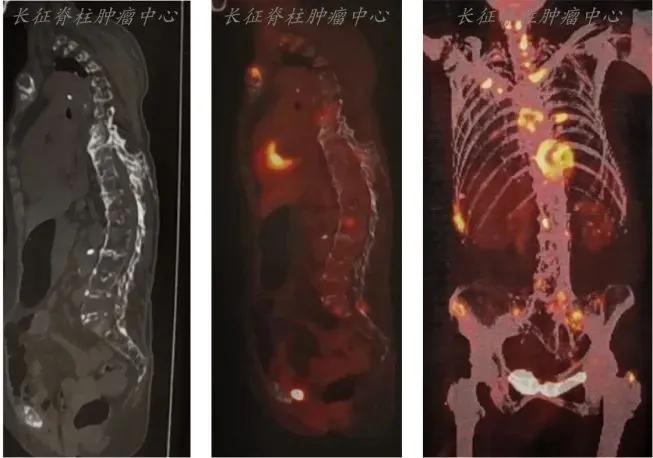

肺癌骨转移是晚期肺癌患者常见的并发症之一,严重影响患者的生活质量和预后。近年来,放射治疗(放疗)在肺癌骨转移的治疗中发挥了重要作用,成为控制症状和延长生存期的重要手段。

放疗在肺癌骨转移治疗中的主要作用是缓解疼痛、预防病理性骨折,并控制局部肿瘤进展。对于骨转移引起的剧烈疼痛,放疗可以迅速缓解症状,提高患者的生活质量。此外,放疗还可以预防骨转移部位发生病理性骨折,降低患者因骨折而需要手术的风险。